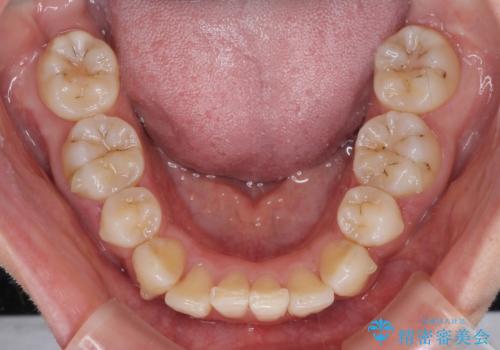

- 以前の矯正治療の後戻りにより、上下の前歯がでこぼこになってしまったことを気にして来院された患者様です。

口元がこれ以上突出することなく前歯の叢生が改善できるよう、歯と歯の間を削ってスペースを獲得し、インビザラインを用いて整えていくこととしました。